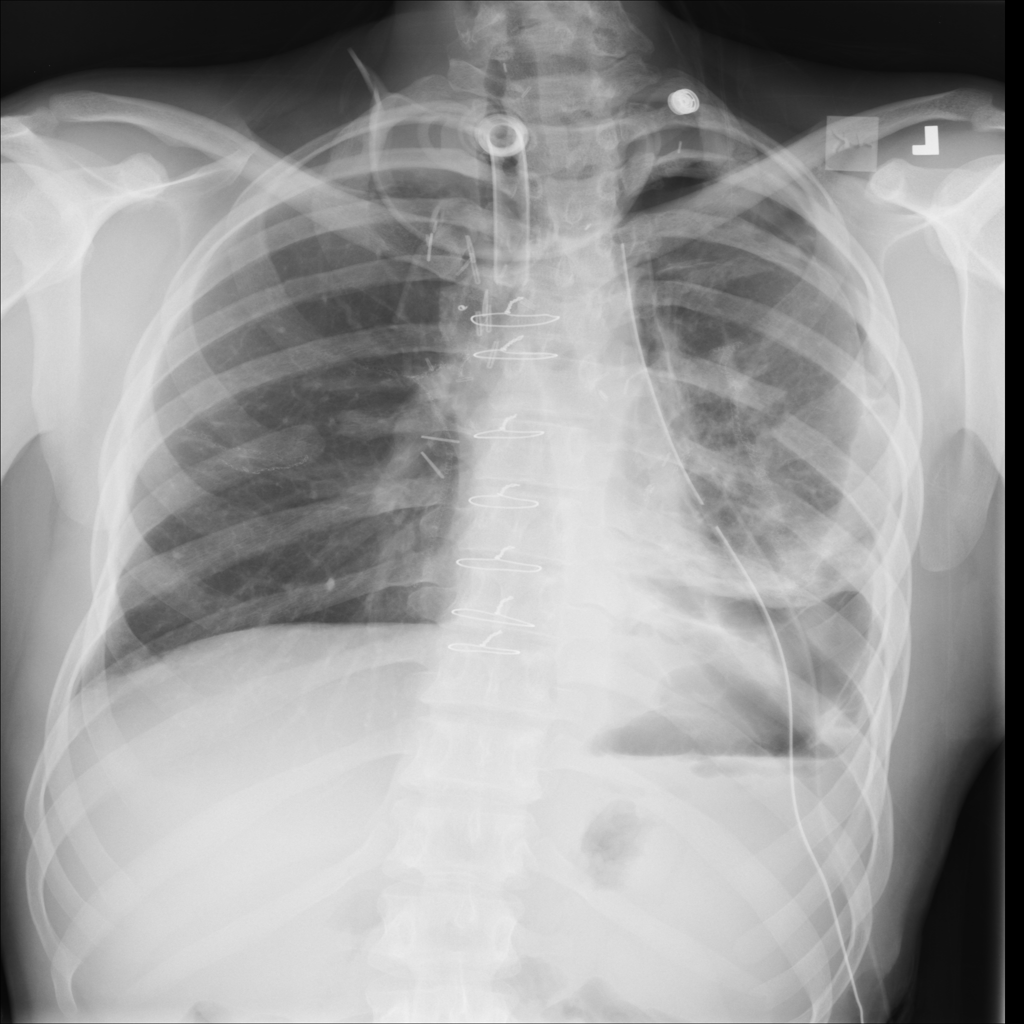

PAT-4639 · IMG-012Pneumothorax

PAT-4639 · IMG-012

AP